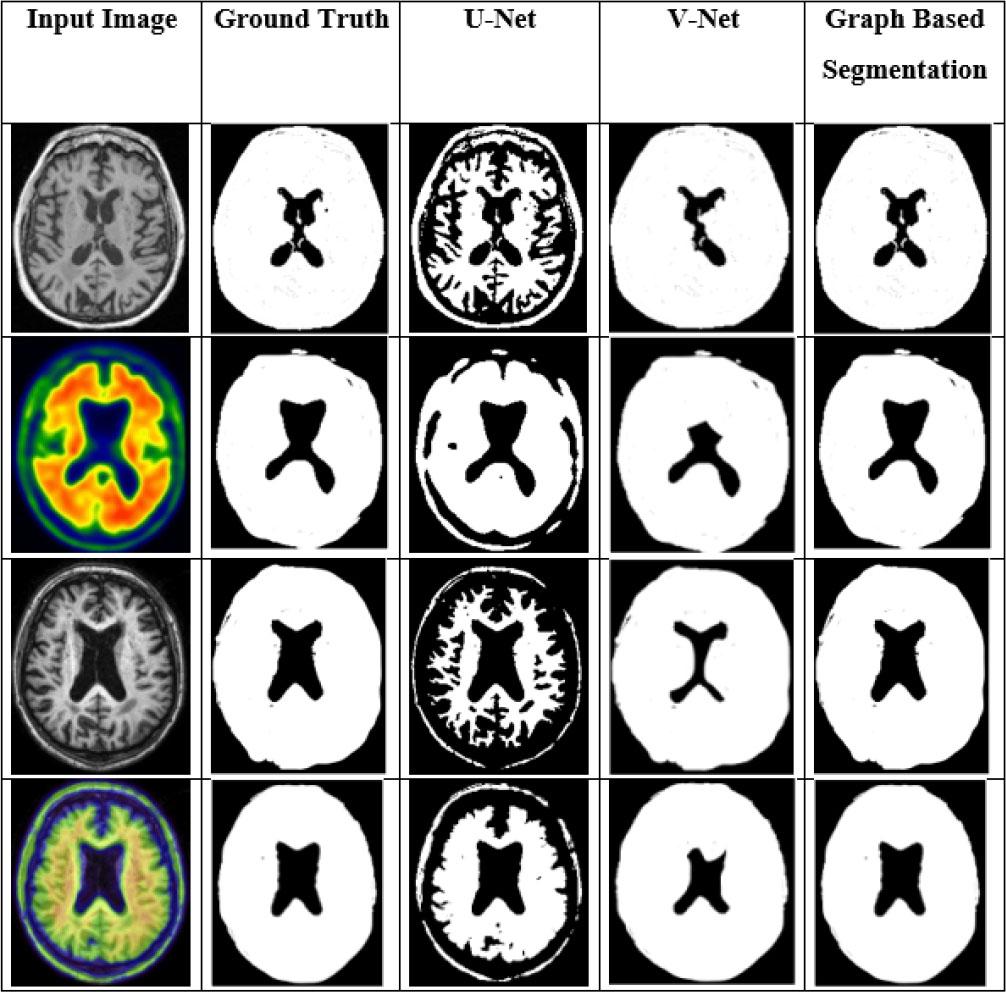

The comparison was conducted with different DL-based segmentation networks using several parameters, as shown in Table 6. The proposed GBS network increases the overall DI by 26.34 %, 11.39 %, 7.66 %, and 5.38 % compared to U-net, V-net, Nested V-net, and SegNet, respectively. The proposed GBS approach outperforms all compared methods, achieving the highest ACC (99.12 %), DI (90.74 %), and intersection over union (IoU) (82.7 %). Traditional segmentation DL-networks did not perform as well as the GBS network.

Fig. 10 displays the visualization outcomes of the different segmentation methods. In this evaluation, the GBS was compared with conventional networks such as V-Net and U-Net. GBS reduces processing complexity and yields better segmentation results than current segmentation techniques.

Comparison results of different segmentation techniques.